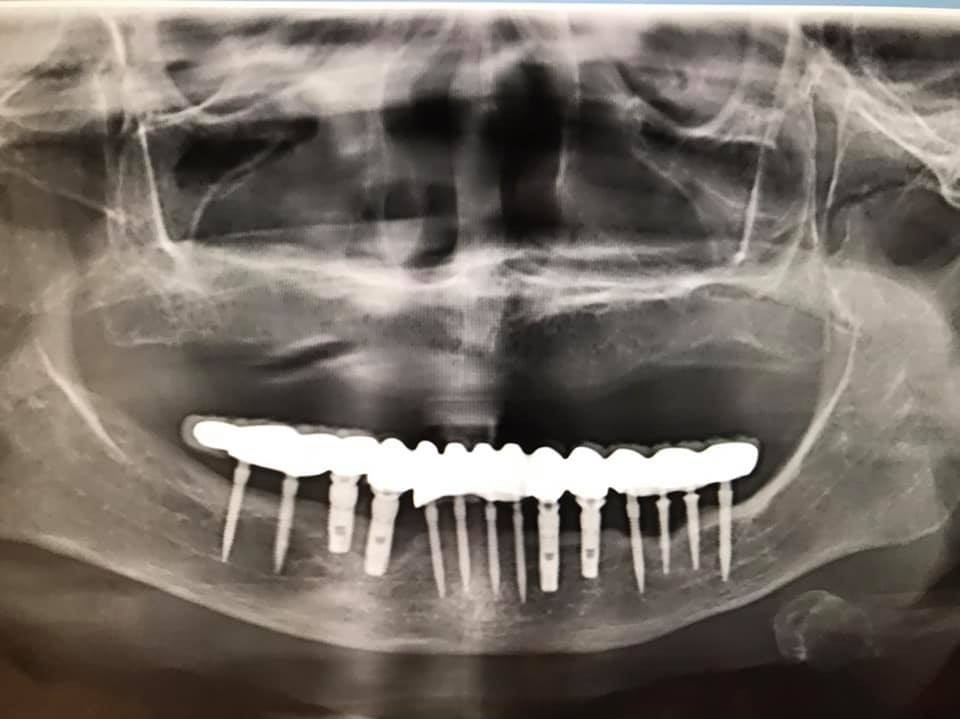

有看過簡易植牙,是用粗針(已不能叫螺絲)當牙根

https://health.ettoday.net/news/1862888

台南爛牙女「滿嘴膿」痛瘋了…植牙2年整排崩壞!全口挖掉燒70萬 | ETtoday健康雲 | ETtoday新聞雲

[圖]

台南一名63歲婦人2年前到診所治療,進行全口植牙,因貪圖便宜使用迷你牙根,沒想到近日發現牙齒反覆腫痛,下顎整排鬆動崩壞,還會流出膿水,嚇得就醫,經醫師診斷,必須拔掉全口的假牙,再燒70萬元全部重新進行植牙手術。 (植牙,牙根,迷你植體,謝孟儒,影音) ...

因為開的洞很小 所以工簡化很多

(原用途是給待植牙 但骨還未長好的人 維持門面用

一旦骨頭長好就取出牙根粗針進行正常植牙)

但以簡易植牙偷工的牙醫 還是少吧